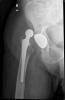

Fractura cuello fémur. Prótesis completa.